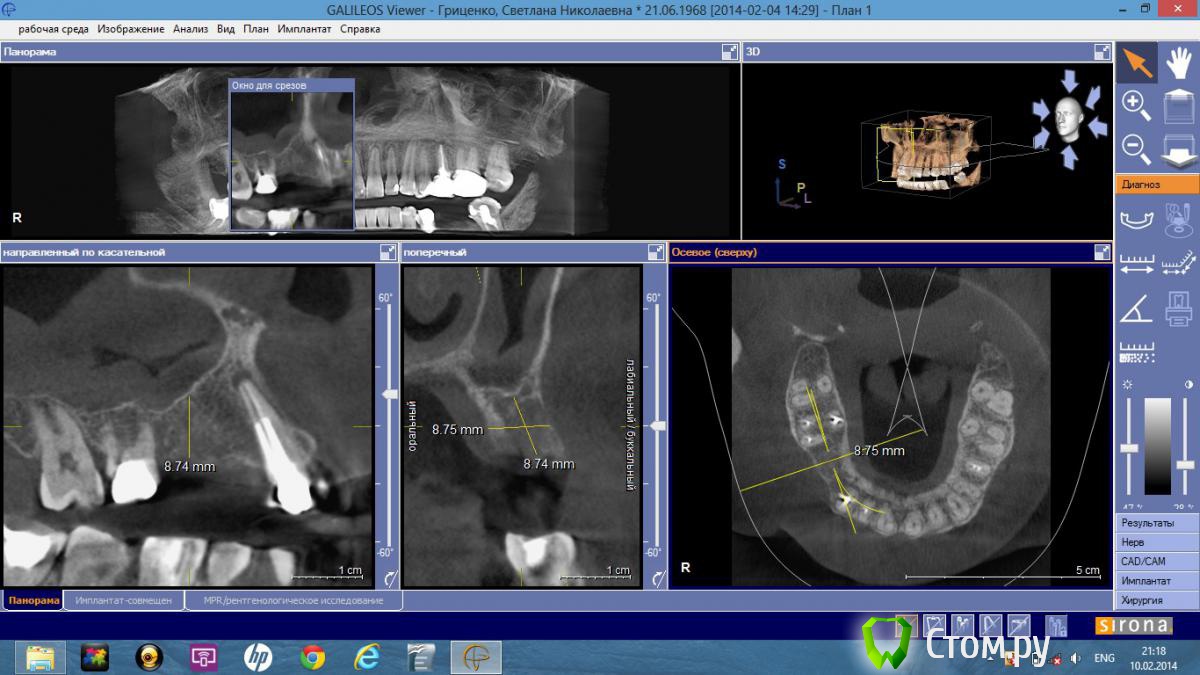

lavrikk Опубликовано 10 февраля, 2014 Поделиться Опубликовано 10 февраля, 2014 Добрый день коллеги! Планируется имплантация в области 1.4 и 1.5. Это моя первая операция на верхней челюсти, помогите с правильным позиционированием и выбором имплантантов. Использую систему Dentium, в области 1.5 хочу поставить 3.8 — 8 мм (без синуса, коронку в дальнейшем как моляр), в 1.4 - 3.4-10 мм. Как бы поступили Вы? Ссылка на комментарий

bullbull Опубликовано 11 февраля, 2014 Поделиться Опубликовано 11 февраля, 2014 Сделал бы 10 мм с закрытым синусом. Направление более вертикально.Что касается 13: подумал бы о повторном эндо и резекции одновременно с имплантацией. 2 Ссылка на комментарий

bullbull Опубликовано 12 февраля, 2014 Поделиться Опубликовано 12 февраля, 2014 В 13 вкладка. Извлечь ее и ортоградно перелечить не представляется возможным. Резекцию лучше проводить одновременно с имплантацией? Просто к разрезу по гребню добавить полулунный в области верхушки или добавить один вертикальный? Для закрытого синуса нет даже остеотомов.какие в этом случае необходимо-вогнутые диаметра имланта? Когда вы начинали многоуважаемые доктора, случались ли у вас в дальнейшем осложнения при установке 8 мм без синуса в этой области?Спасибо за добрые советы!Тогда на 15 3,8х8 мм, на 14 - 3,4х12. Выбор остеотомов зависит от качества кости. Если очень мягкая, то можно после пилота (2-2,5 мм) расширять только остеотомами. Для диаметра 3,8 остановился бы на остеотоме 3,5, при 3,4 - 3,0. Осложнений быть не должно. Прогноз благоприятный. Если торк больше 35, можно заканчивать ФДМ или коронками.При подобных изменениях поднятие на 2 мм не смертельное. Хотя, иногда слизистая бывает рыхлая и просто прокалывается остеотомом. В такой ситуации на дно костного ложа кладу ОбТП и ставлю винт. Ссылка на комментарий